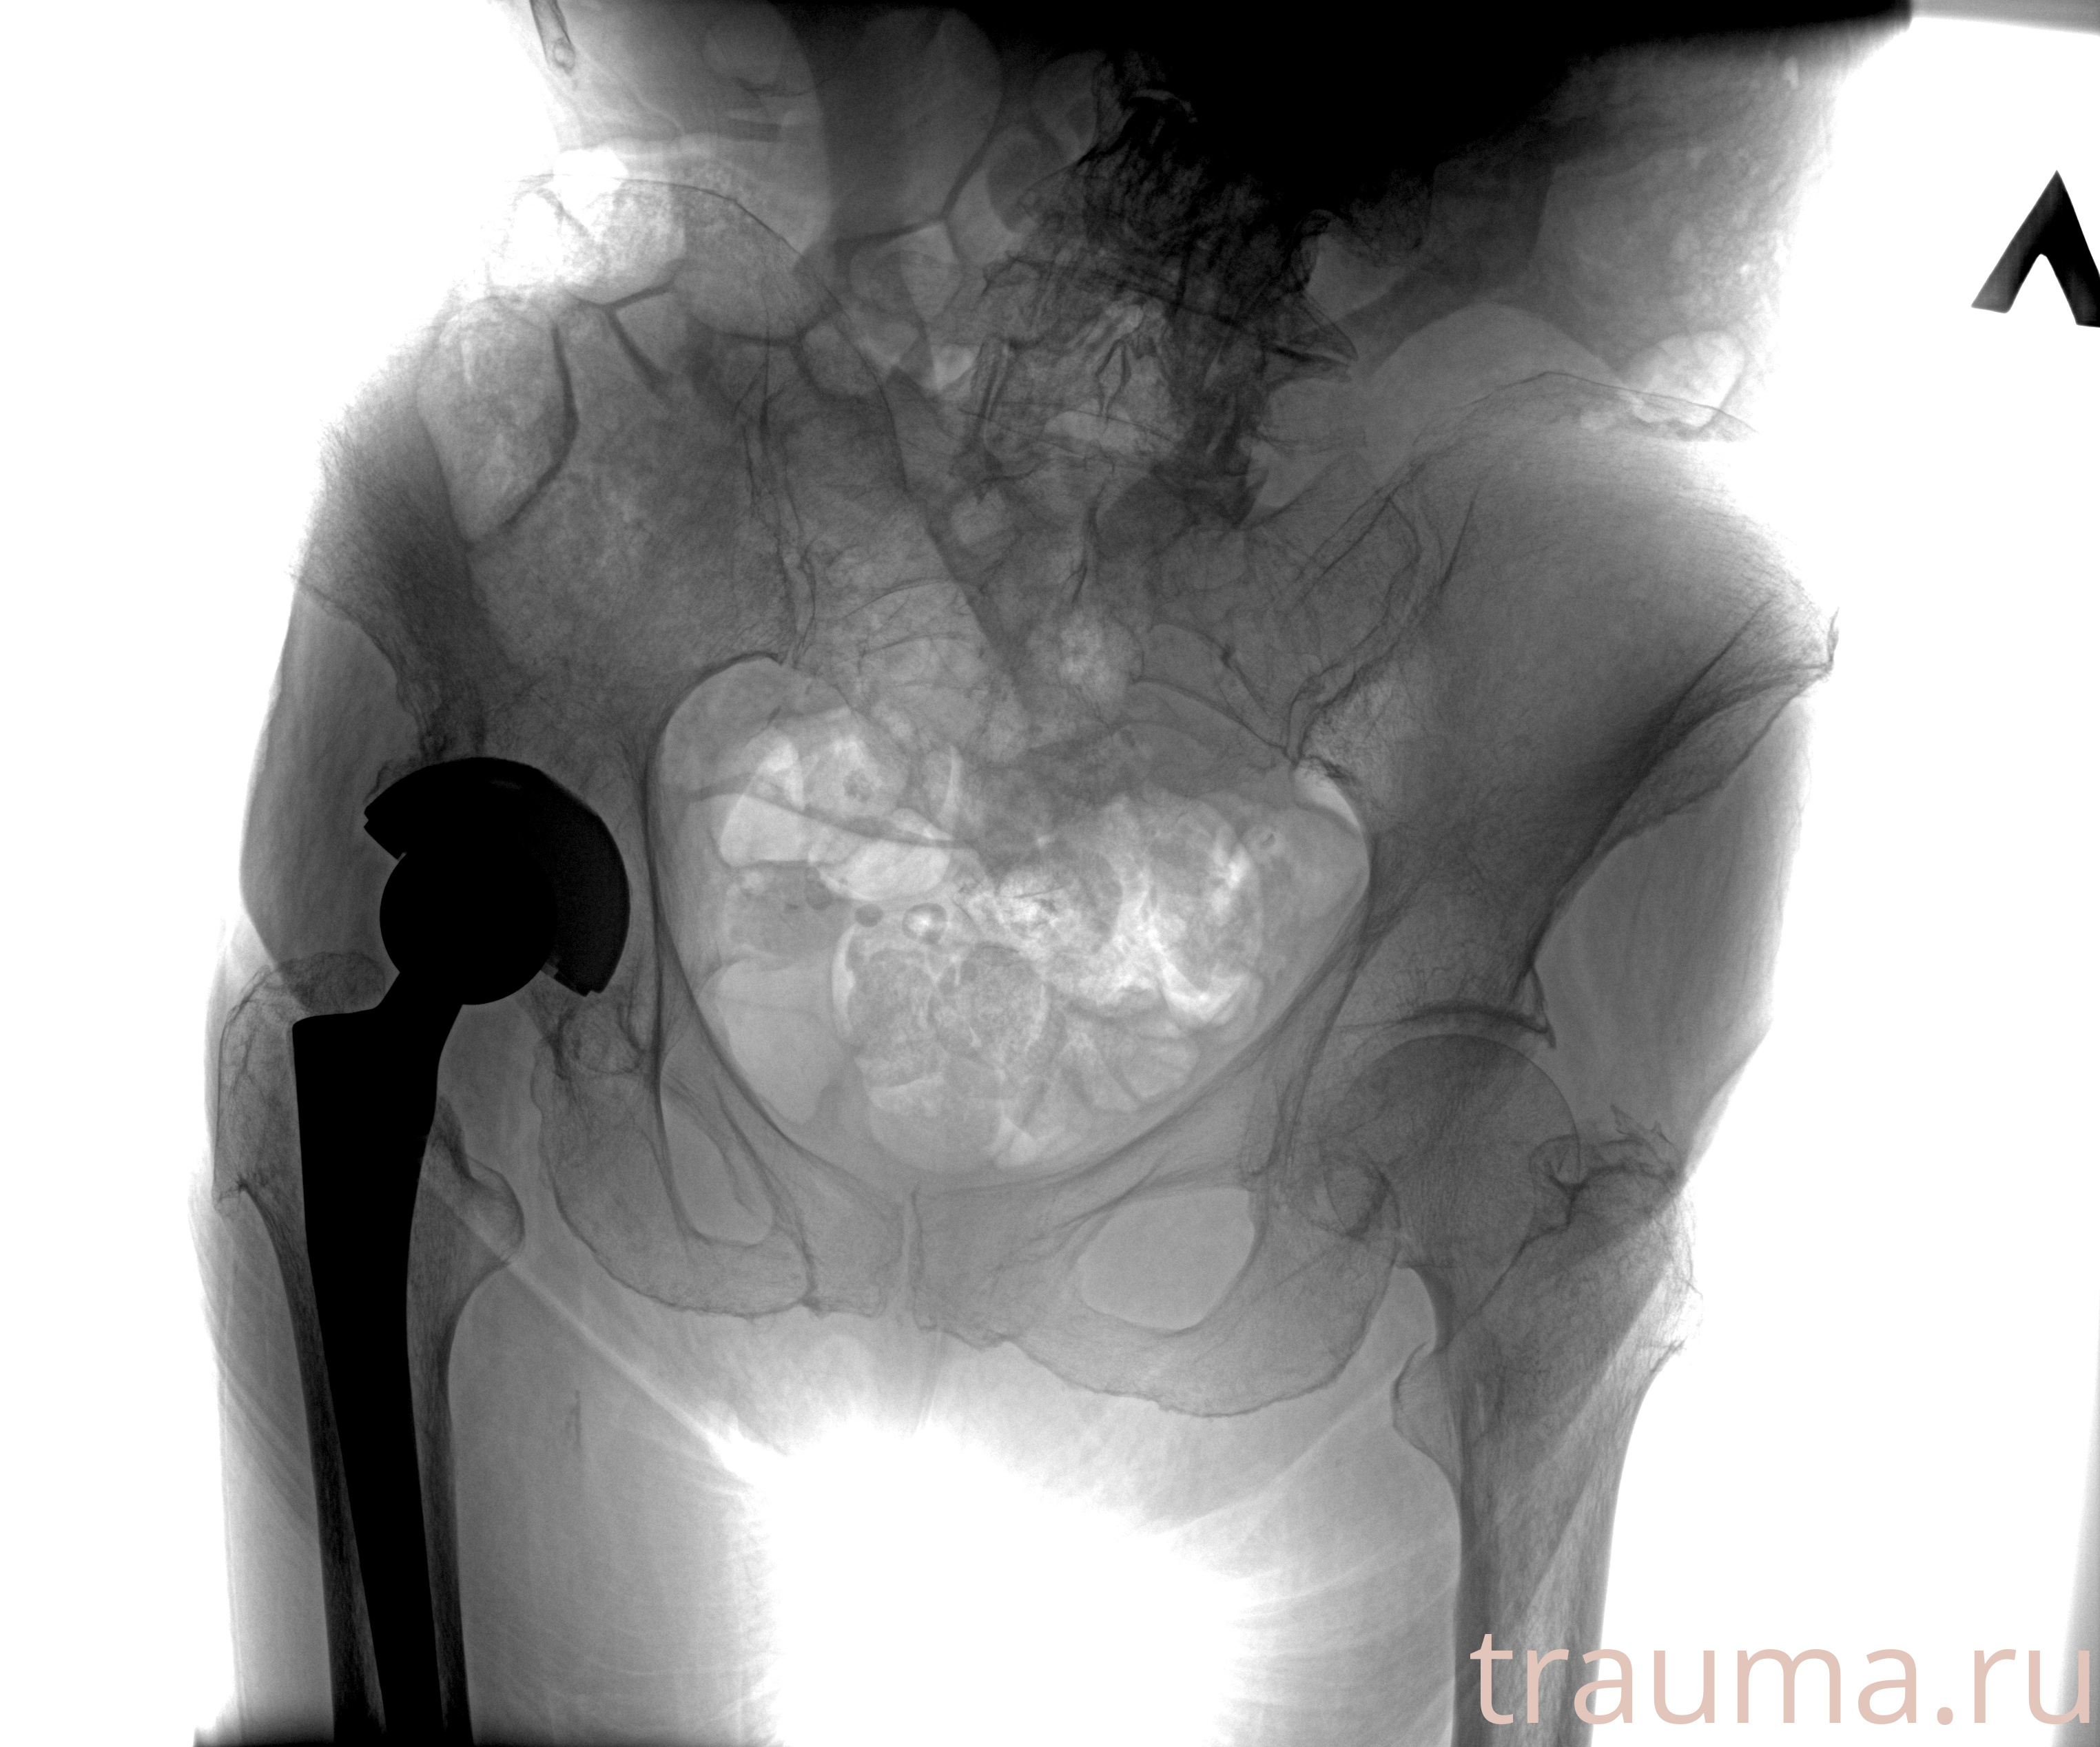

Рентгенограммы

Рентген на дому: по вашему адресу приезжает врач-рентгенолог, травматолог-ортопед с мобильным рентгеновским аппаратом, проводит диагностику травмы или заболевания, делает необходимые рентгенограммы, дает рекомендации по дальнейшему лечению. Получить качественные снимки в домашних условиях возможно благодаря уникальной методике, разработанной МосРентген Центром для института  Склифосовского